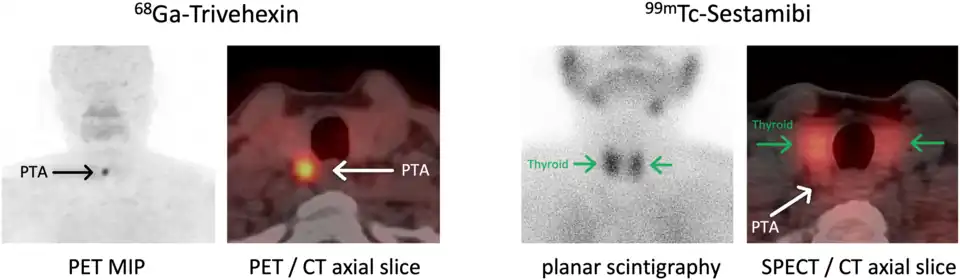

Lokalisationsdiagnostik

Vor einer geplanten Operation können Lokalisation und Größe der betroffenen Nebenschilddrüsenkörperchen durch Sonografie, Szintigrafie mit Technetium-99m-Sestamibi (Nebenschilddrüsenszintigrafie), Computertomographie oder Kernspintomografie dargestellt werden.

Die Sensitivität dieser diagnostischen Verfahren ist jedoch begrenzt. Besonders bei komplizierteren Fällen, wie zum Beispiel bei Vorhandensein von mehreren auffälligen Nebenschilddrüsen oder entfernt auftretenden Nebenschilddrüsenadenomen, kann eine zuverlässige Lokalisation aller betroffenen Epithelkörperchen schwierig sein.[60] Neuere bildgebende Verfahren, wie Positronenemissionstomographie (PET) mit speziellen Radiopharmaka wie 68Ga-Trivehexin, können in solchen Fällen eine zuverlässigere Lokalisation ermöglichen,[61] wodurch deren komplette chirurgische Entfernung und damit eine vollständige Heilung des primären Hyperparathyreoidismus wahrscheinlicher wird.